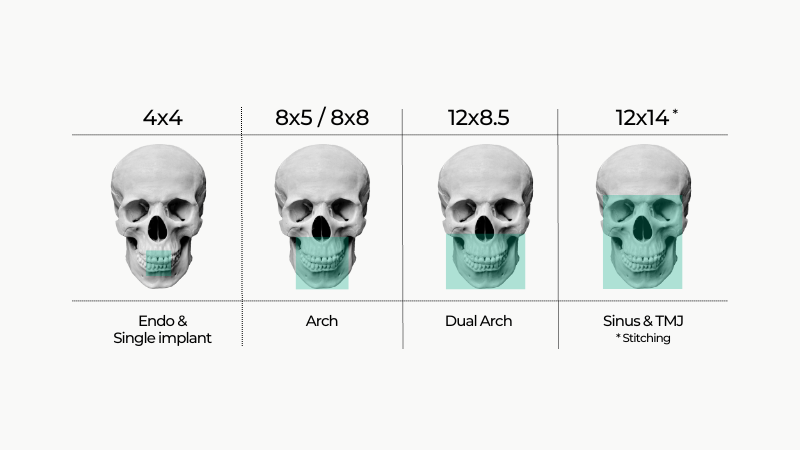

- Selectarea Multi-FOV

Dispozitivul oferă 5 opțiuni de câmp vizual (FOV) între 4×4 cm și 12×8,5 cm, toate cu doză redusă. Cu funcția Double Scan, puteți extinde imaginea la 12×14 cm pentru o analiză completă a arcului dentar, inclusiv articulația temporo-mandibulară (ATM).

- Dimensiuni FOV:

- 4×4 cm (endo, Smart Focus)

- 8×5 cm, 8×8 cm

- 12×8,5 cm (Smart Focus)

- 12×14 cm (Double Scan)